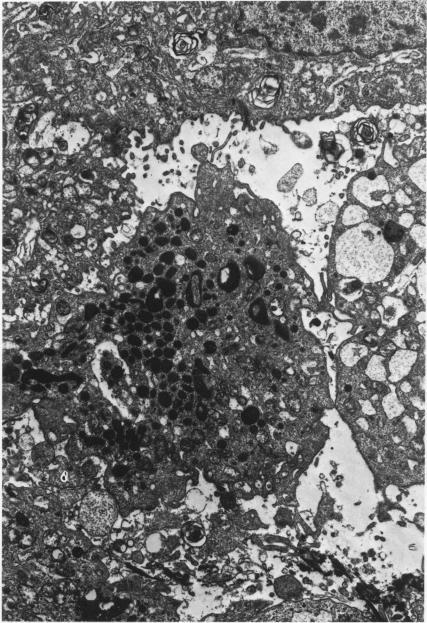

Desquamative interstitial pneumonia. An electron microscopic study.

Am J Pathol. 1970 Sep;60(3):347-70.